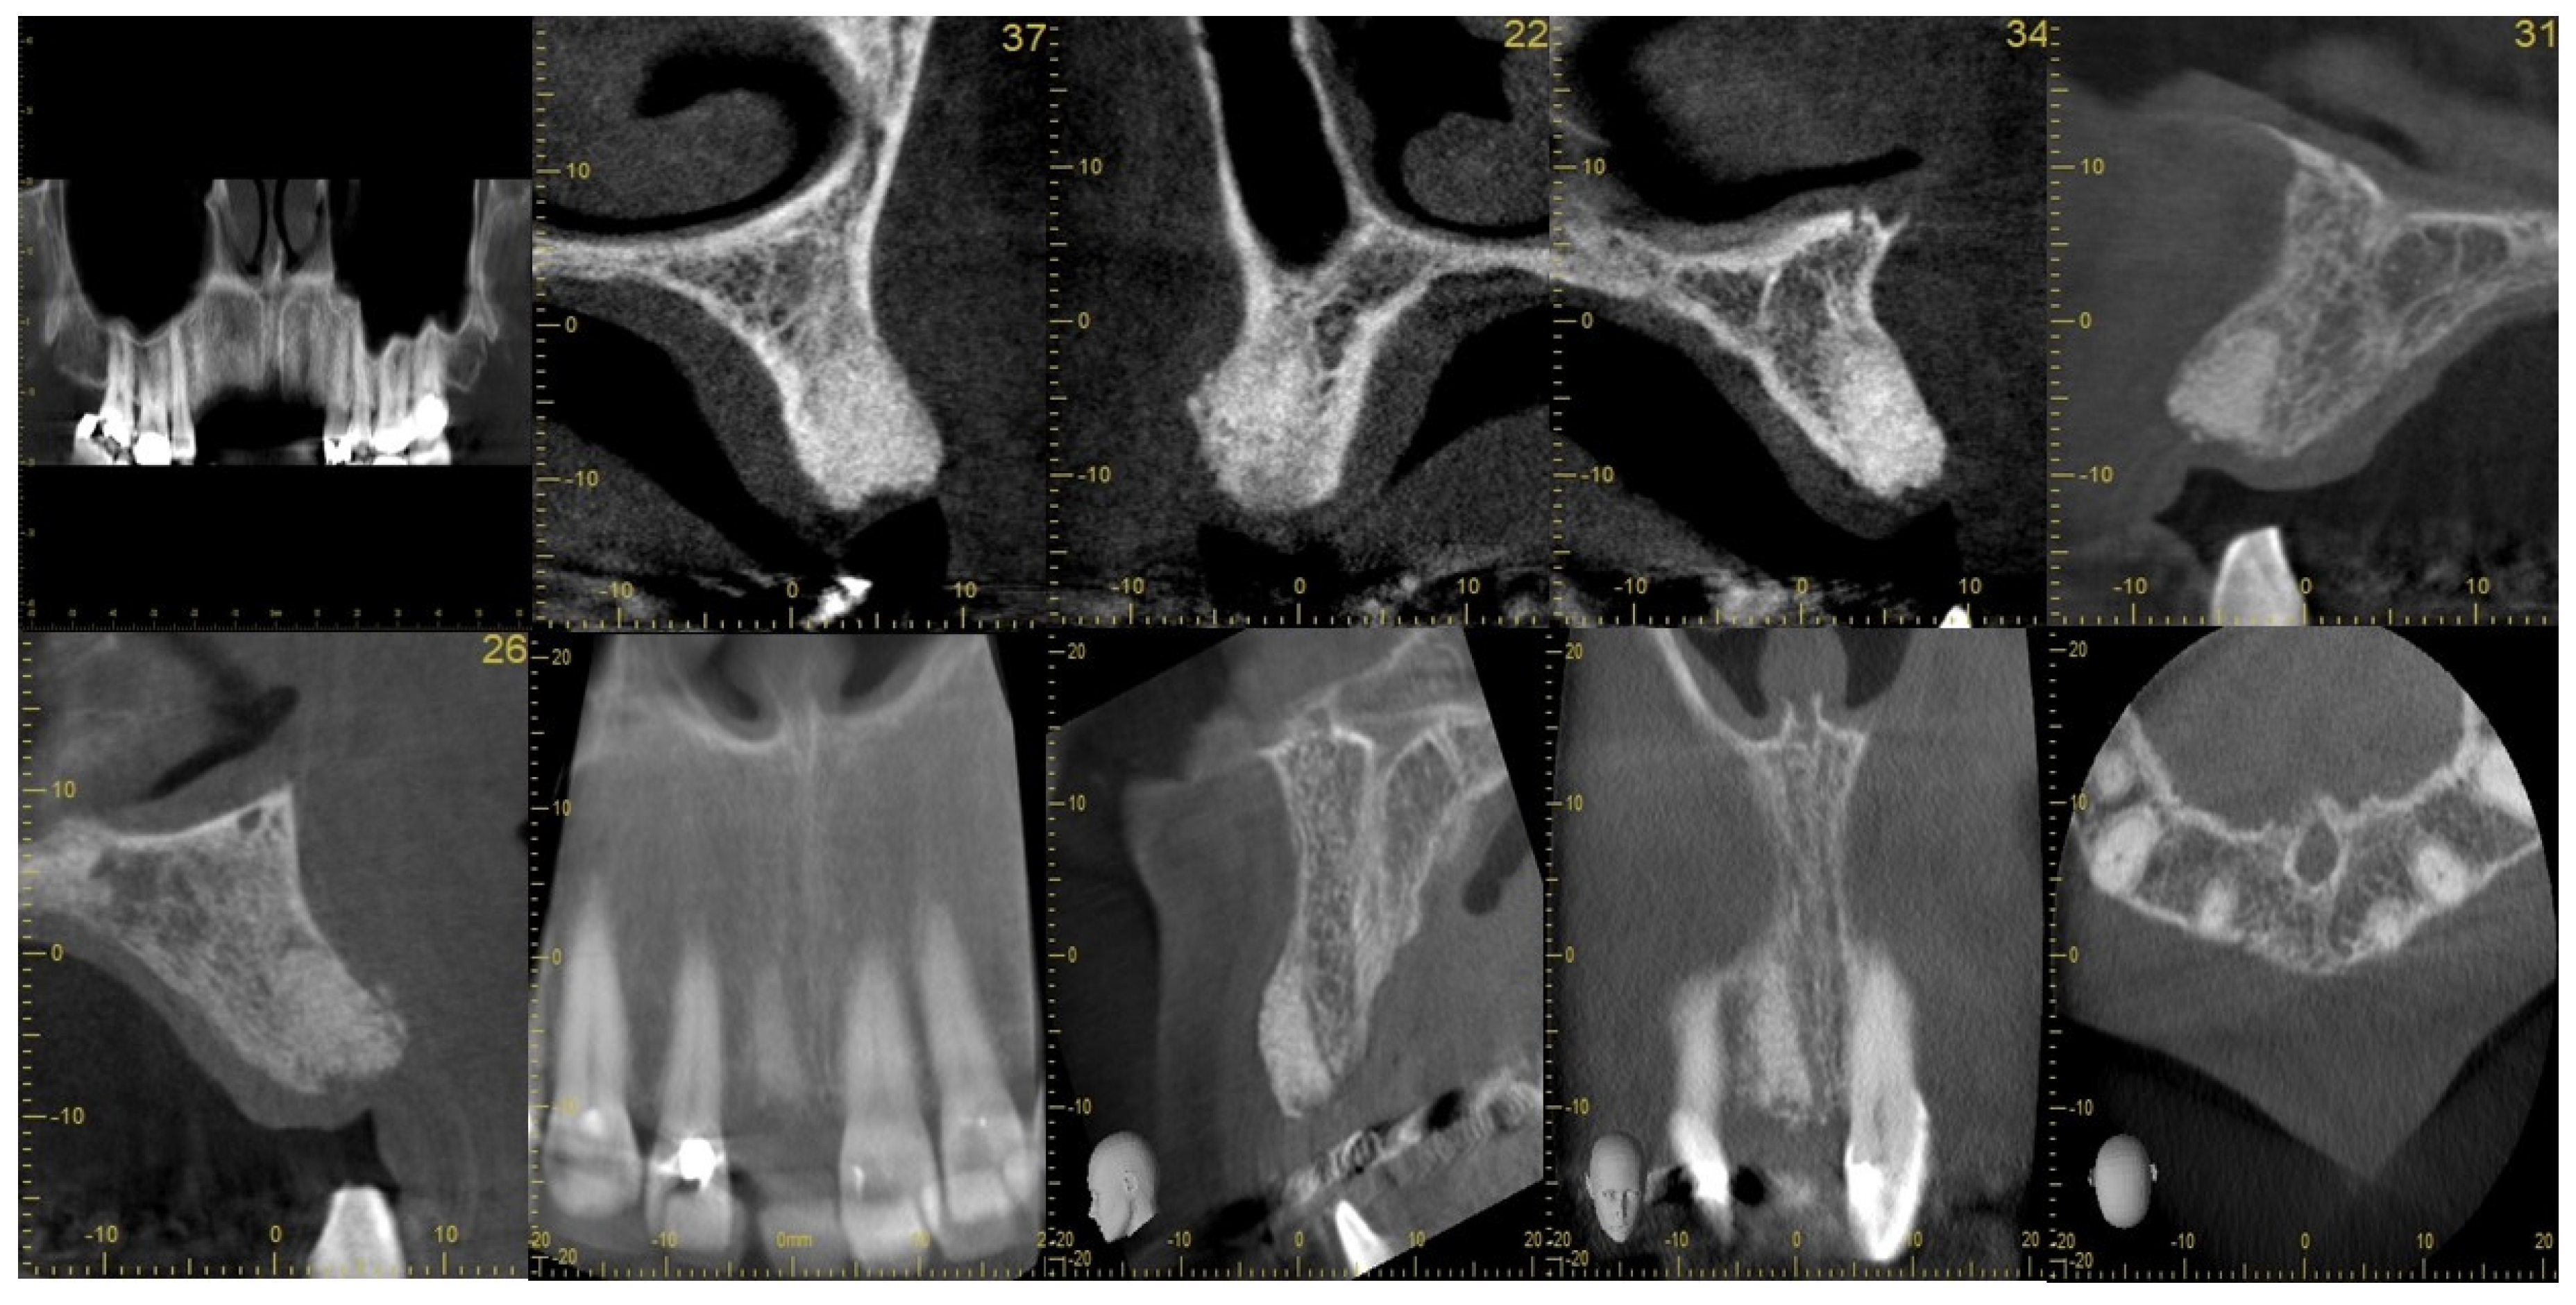

2.2. Case Study

| Step 1 | Assess alveolar ridge condition and morphology clinically and radiologically

|

| Step 2 | Extract using minimally invasive technique and clean and irrigate the extraction socket

| Step 3 | Augment and suture